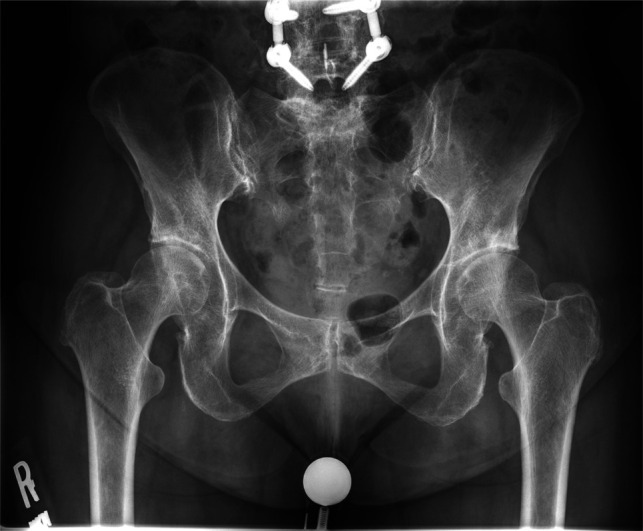

摘要非外伤性双侧股骨头坏死(ONFH)是一种罕见的现象,其病因尚未完全了解。在本报告中,我们描述了一例75岁的女性患者,在关节内皮质类固醇注射后发展为快速发作的双侧ONFH。患者接受分阶段双侧全髋关节置换术。术后几个月,患者出现左侧股骨假体无菌性松动,需要对其股骨假体进行翻修。在最初的手术处理中,她的骨坏死的严重程度和远端程度并没有得到充分的认识,这可能增加了她股骨植入物骨整合失败的风险。本病例表明,关节内皮质类固醇注射可导致严重的ONFH,并延伸至股骨近端并导致固定失败。因此,股骨近端骨坏死的程度可能影响茎的选择。

Atraumatic bilateral osteonecrosis of the femoral head (ONFH) is a rare phenomenon whose etiology is not fully understood. In this report, we describe the case of a 75-year-old female patient who developed rapidly onset bilateral ONFH after intra-articular corticosteroid injections. She was treated with staged bilateral total hip arthroplasty. Several months post-operatively, she developed aseptic loosening of the left femoral implant and requiring revision of her femoral implant. The severity and distal extent of her osteonecrosis was not fully appreciated upon initial surgical management, likely increasing her risk of failure of femoral implant osseous integration. This case demonstrates that intra-articular corticosteroid injections can cause severe ONFH with extension into the proximal femur and fixation failure. Thus, the extent of osteonecrosis in the proximal femur may influence stem choice.